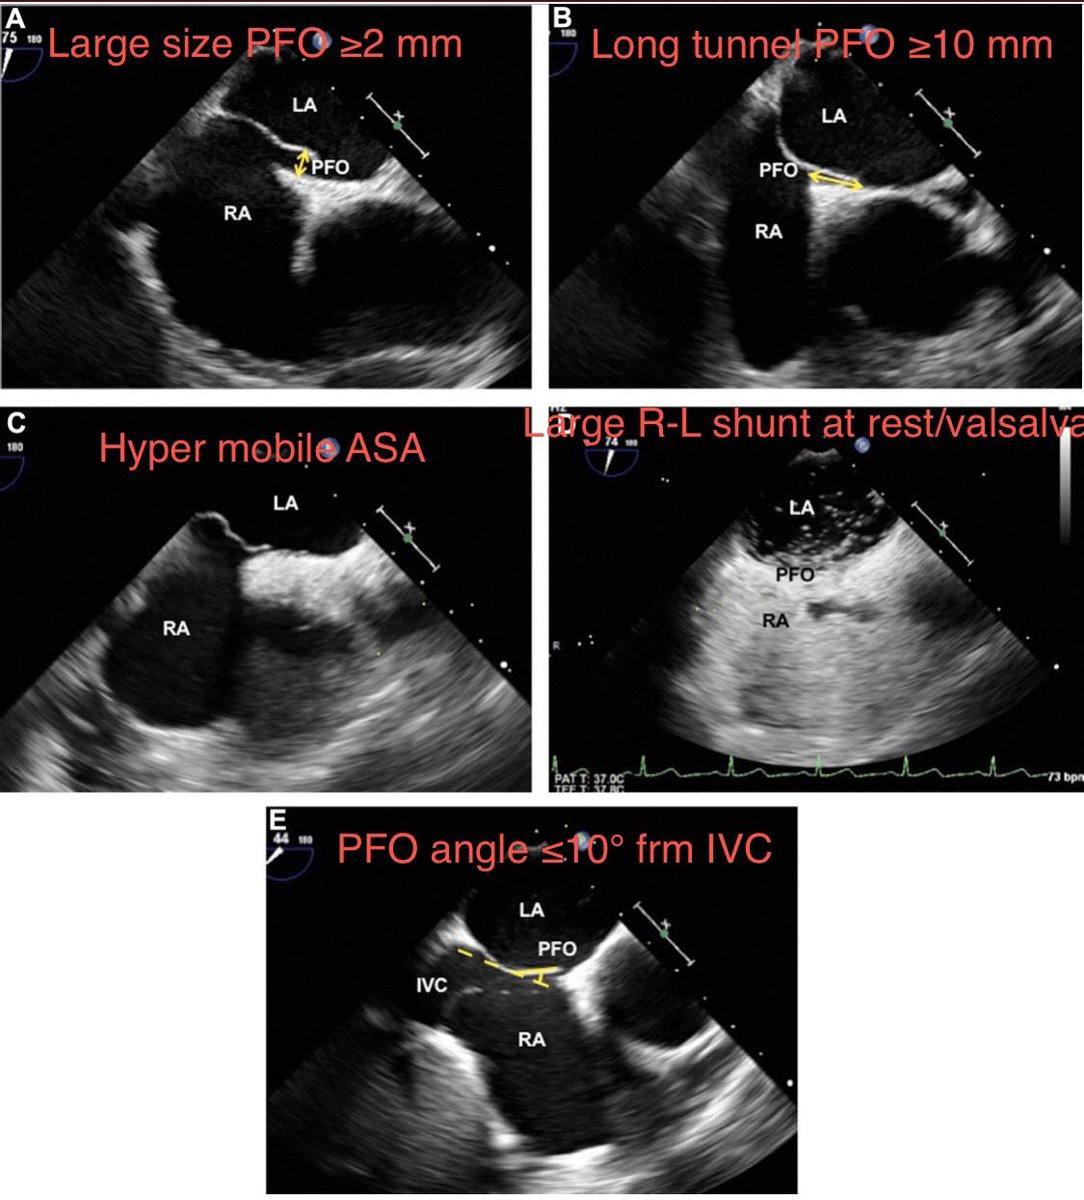

Lily Zhang Enrique Garcia-Sayan, MD, FACC, FASE JASE RTHahnMD Edward Gill American Society of Echocardiography PFO risk score for cryptogenic stroke(if score ≥2) each worth 1 pt: large-size PFO ≥2 mm long-tunnel PFO ≥10 mm ASA hypermobile ASA prominent eustachian valve/Chiari's network large R-L shunt at rest/Valsalva PFO ≤10° frm IVC #ASEchoJC bit.ly/3Hm1RJ3

<a href="/LilyLeiZhang1/">Lily Zhang</a> <a href="/EGarciaSayan/">Enrique Garcia-Sayan, MD, FACC, FASE</a> <a href="/JournalASEcho/">JASE</a> <a href="/hahn_rt/">RTHahnMD</a> <a href="/edwardagill/">Edward Gill</a> <a href="/ASE360/">American Society of Echocardiography</a> PFO risk score for

cryptogenic stroke(if score ≥2)

each worth 1 pt:

large-size PFO ≥2 mm

long-tunnel PFO ≥10 mm ASA

hypermobile ASA

prominent eustachian valve/Chiari's network

large R-L shunt at rest/Valsalva

PFO ≤10° frm IVC #ASEchoJC bit.ly/3Hm1RJ3